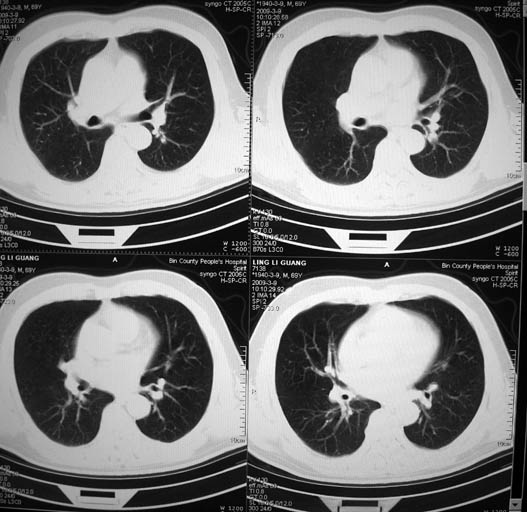

以下是引用随光逐影在2009-3-9 21:36:00的发言:[br]1)两肺上叶尖段结节状病灶,性质待定(不排除肿瘤可能);建议追踪复查。2)右肺中叶内侧段炎症。